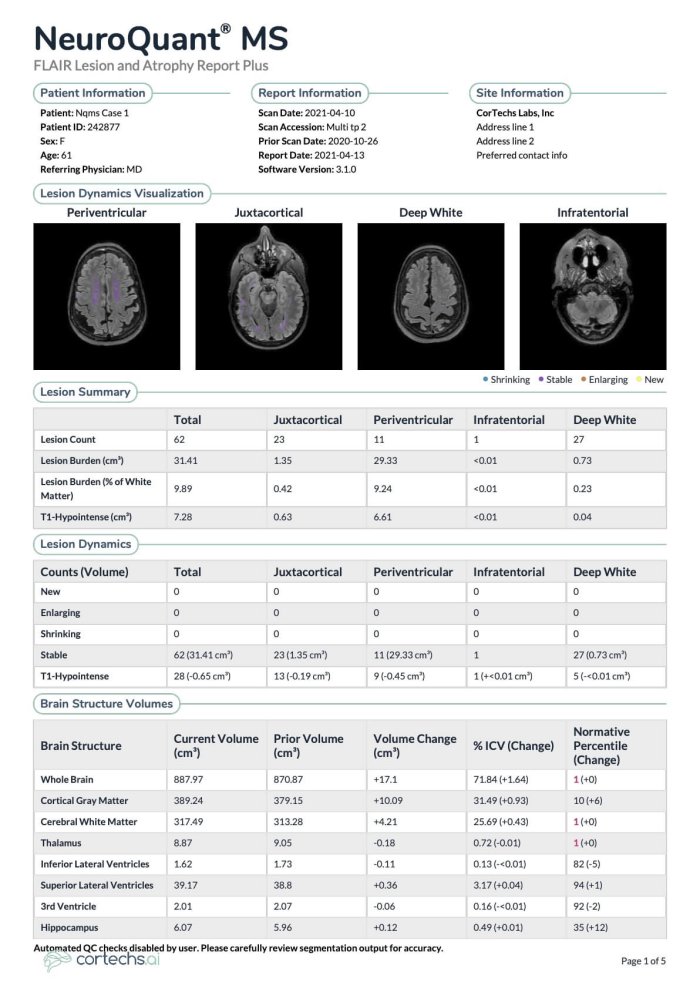

For the assessment of multiple sclerosis and other neurodegenerative conditions. Automatically label, visualize and obtain the volumetric quantification of segmentable brain structures and lesions from MRI brain studies—within minutes. NeuroQuant MS combines T2 FLAIR with 3D T1 MR images to enhance your ability to identify and monitor the number and progression of brain lesions. Accurately visualizing lesions and lesion volume change enables you to deliver an efficient, objective assessment of disease activity, so you can determine the best course of treatment more quickly.

If a patient ID is already in the system, NeuroQuant will pull prior data to perform ongoing multi-time point evaluations to assess brain structure volume changes over time—all indicated on the same report.

Normative Reference Data